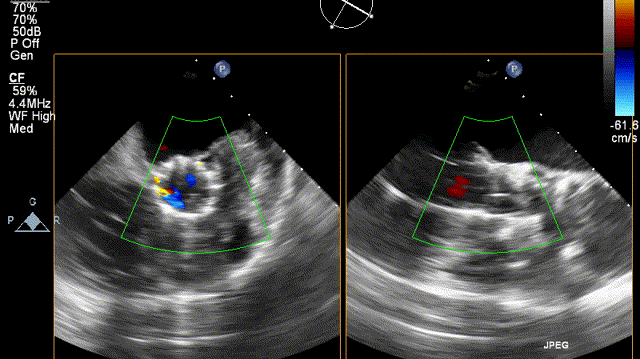

超声检查

超声结果显示主动脉瓣退行性病变,重度狭窄并轻度反流;主动脉瓣瓣口流速5.9m/s,峰值跨瓣压差138mmHg,平均跨瓣压差72mmHg,瓣环内径20mm,升主增宽,主动脉弓内径36mm,反流彩束面积2.3cm²,LVOT-VTI:28.9cm。此外,患者同时合并左室壁增厚,左室舒张功能减退,节段性室壁运动异常,重度二尖瓣反流,重度三尖瓣返流,轻度肺高压。

主动脉根部TEE评估